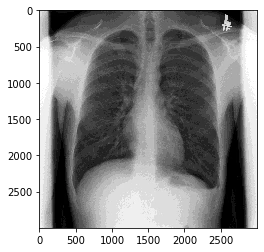

Scikit-image

# skimageを使う

import skimage

sk_img = skimage.img_as_ubyte(pixels)

plt.imshow(sk_img,cmap="gray")#2つとも必要

plt.show()

お!と思うが、これはまやかしで、よくみると画素が潰れている。